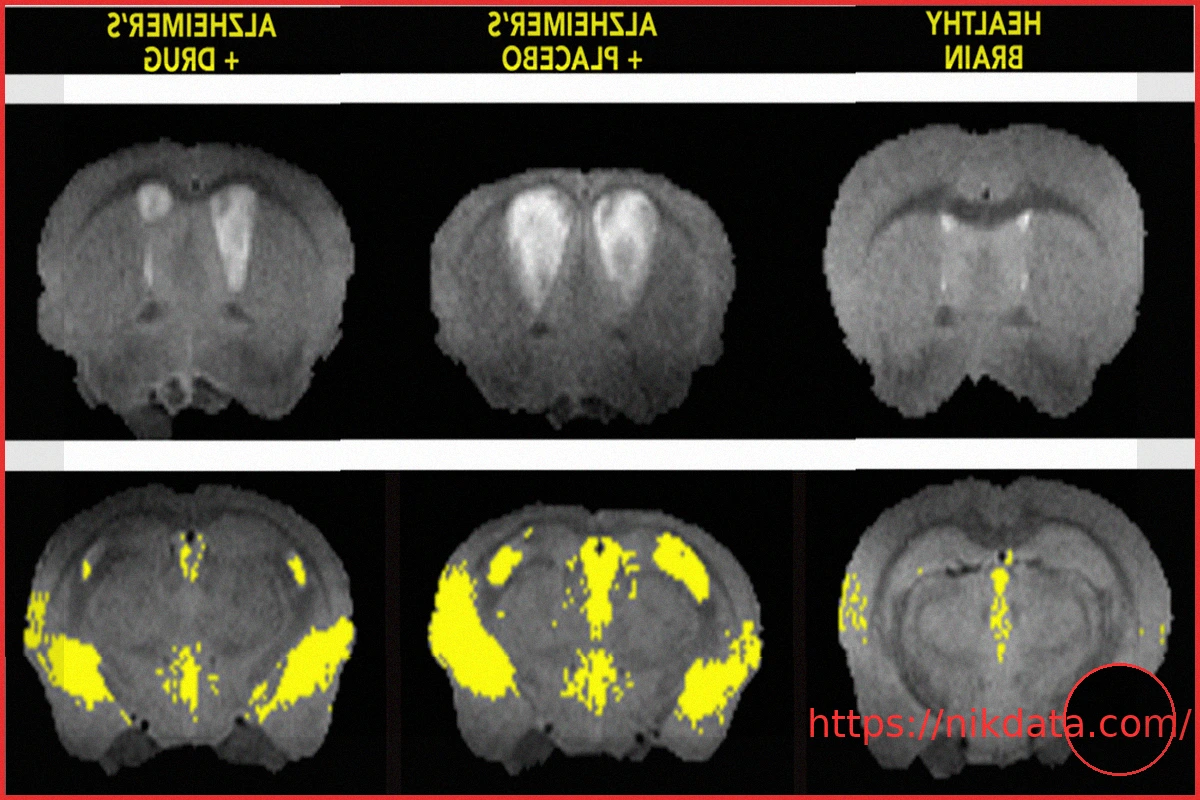

Researchers have identified a previously unseen ‘death switch’ within the brain, potentially a key driver of Alzheimer’s disease. Remarkably, they’ve also demonstrated a method to deactivate it in mouse models. This mechanism involves a harmful interaction between two specific proteins. When these proteins bind together, they initiate the destruction of vital brain cells, leading to memory impairment. Through the application of a novel compound designed to disrupt this damaging protein partnership, the scientists observed a significant slowing of disease progression, enhanced protection for brain cells, and even a reduction in the characteristic amyloid plaque accumulation.